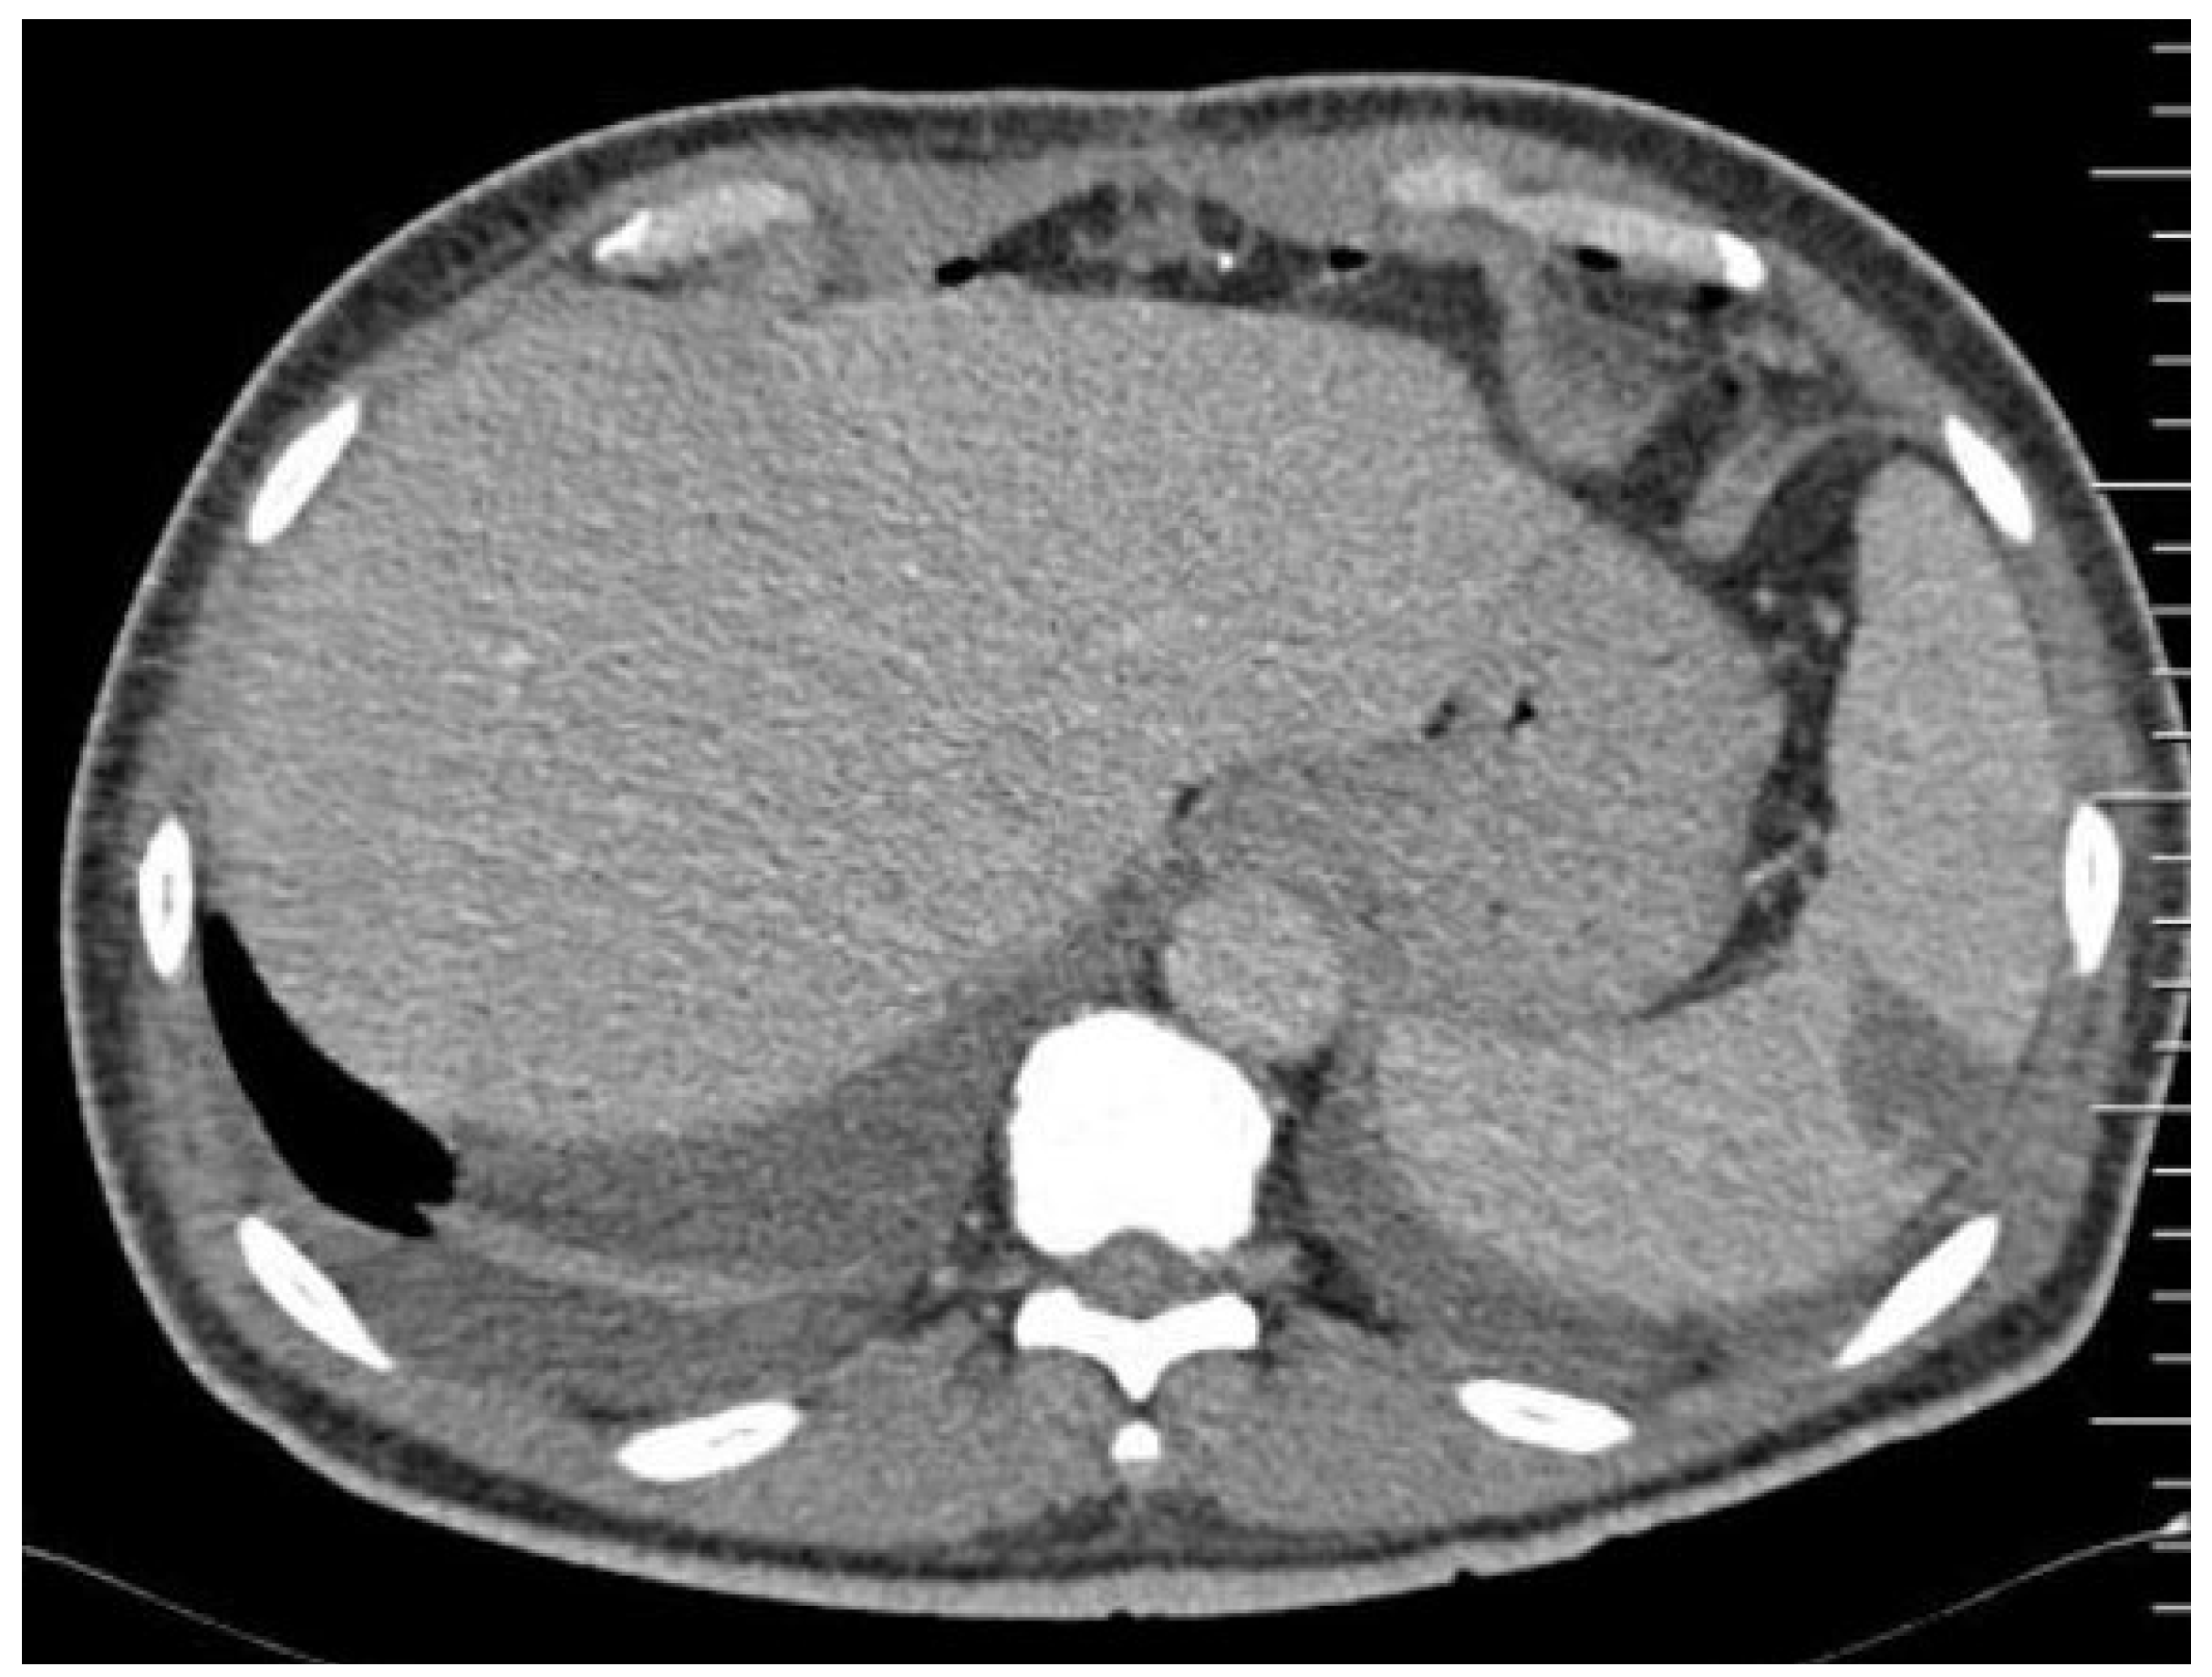

- Vancauwenberghe, T.; Snoeckx, A.; Vanbeckevoort, D.; Dymarkowski, S.; Vanhoenacker, F.M. Imaging of the spleen: What the clinician needs to know. Singap. Med. J. 2015, 56, 133–144. [Google Scholar] [CrossRef] [PubMed]

- Peddu, P.; Shah, M.; Sidhu, P.S. Splenic abnormalities: A comparative review of ultrasound, microbubble-enhanced ultrasound and computed tomography. Clin. Radiol. 2004, 59, 777–792. [Google Scholar] [CrossRef]

- Colen, T.W.; Gunn, M.; Cook, E.; Dubinsky, T. Radiologic manifestations of extra-cardiac complications of infective endocarditis. Eur. Radiol. 2008, 18, 2433–2445. [Google Scholar] [CrossRef] [PubMed]